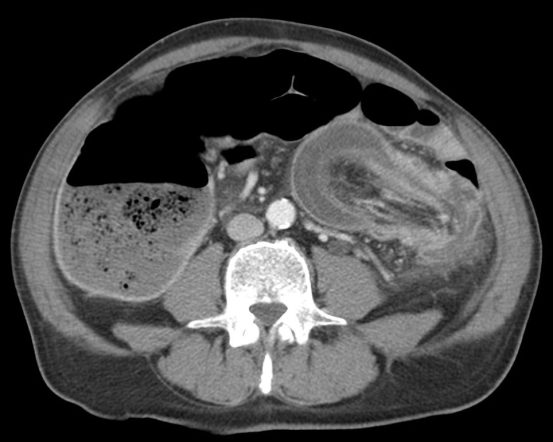

- El hallazgo patognomónico es el signo de la escarapela o diana identificable en la TC o ecografía.

- Podemos ver la imagen de «Intestino dentro de intestino” gracias a las reconstrucciones multiplanares.